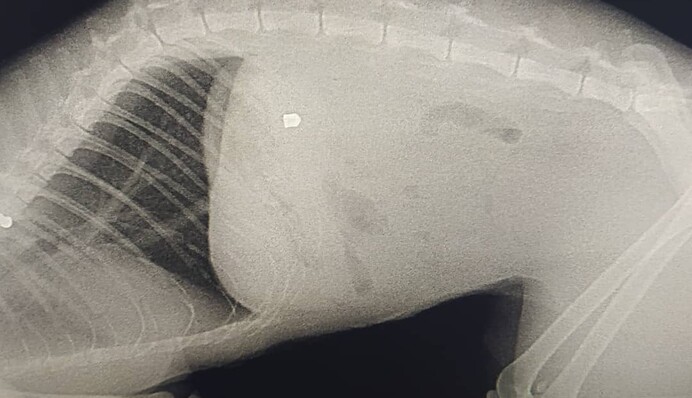

"Вчора кіт ввечері прийшов з раною на животі. Ми повезли його в клініку. Там сказали, що це постріл з воздушки і що ми не перші, хто до них звертається з такою проблемою з нашого району", - йдеться в повідомленні.

Це вже восьмий подібний випадок в районі. Коту надали допомогу, потім провели операцію в іншій лікарні. Воздушка виявилася незвичайною, шансів було всього 20%. На щастя, все пройшло успішно, але коту знадобиться багато часу на відновлення.